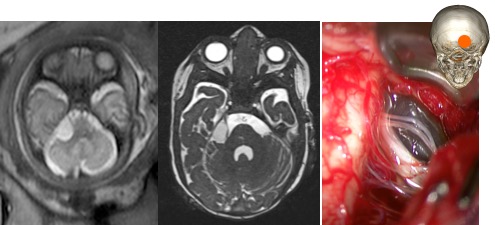

on regroupe sous ce terme des kystes dont la paroi n’est pas méningée mais constituée de tissus cérébraux. il s’agit d’un ensemble très divers de pathologies rares, qui peuvent être diagnostiquées en anténatal.